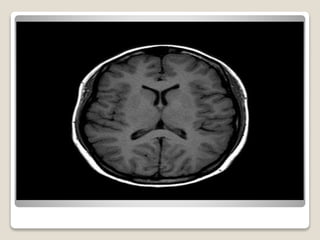

RM CRÂNIO

 Estudo neurológico

 Exame ouro pra estudo

do crânio

 Exame mais utilizado

Medula oblongaPonte

Mesencéfalo

Hipófise

Giro do cíngulo Sulco

Parieto-occipital

v.galeno

Pineal

Radiação

óptica

Hipocampo

Cápsula interna

Lobo temporal

Ventrículo lateral

(corno temporal)

Região

insular

Lobo parietal

Lobo frontal

(corpo)

Coroa radiada

Núcleo caudado

(cabeça)

Fórnix

Cerebelo

Vermis

Tenda do